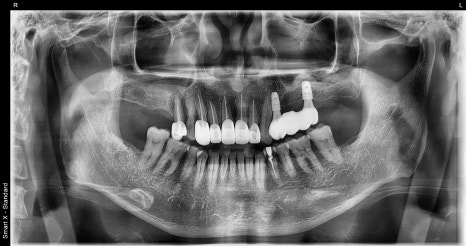

🖼️ Before-and-after comparison photos

Before-and-after panoramic X-ray comparison (left: first visit / right: after treatment)